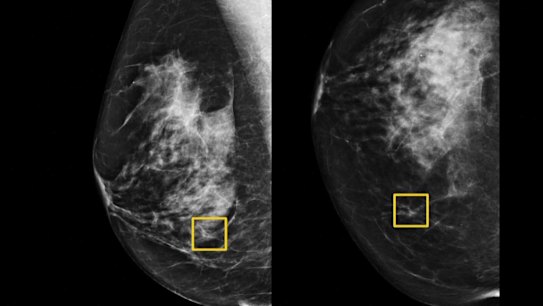

Progress has slowed for colorectal, breast and prostate cancers, however.

The rising rate of obesity among Americans, as well as significant racial and geographic disparities, likely explain why the decline in breast and colorectal cancer death rates has begun to taper off, and why the decrease in rates of prostate cancer has halted entirely.